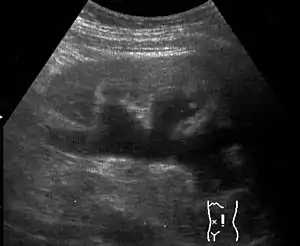

Massive hydronephrosis as marked by the arrow.- Renal ultrasonography of hydronephrosis[14]